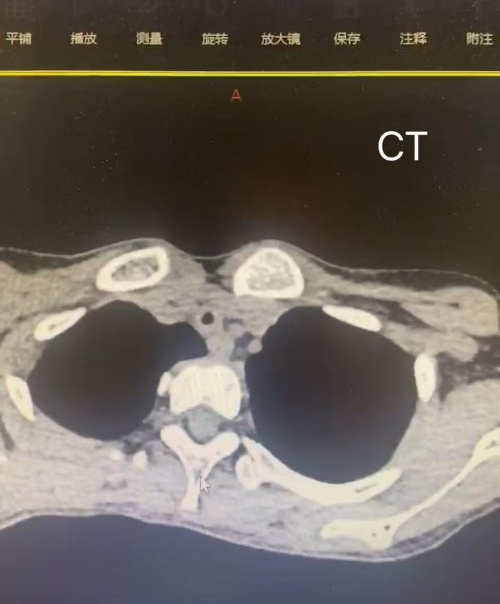

据悉,该患儿因“呼吸困难持续19天”紧急入院,其2个月前曾因糖尿病酮症酸中毒并呼吸衰竭接受有创机械通气治疗。入院后,呼吸科团队快速完善胸部CT及气道三维重建、支气管镜等检查,确诊其气管中下段存在严重狭窄——最窄处达70%,狭窄段长度约1.3厘米,这是导致患儿持续呼吸困难的核心原因,病情危急且治疗难度极大。面对复杂的临床挑战,医院迅速启动多学科会诊机制。在副院长张同强的统筹指导下,呼吸科联合耳鼻咽喉科、麻醉科及手术护理团队制定精细化治疗方案,并特邀气道介入领域专家杨鹏主任到院全程指导手术。

作为四级高难度手术,支气管镜下气道介入治疗对操作精度与团队协作能力要求极高。手术中,医疗团队在支气管镜直视下精准定位狭窄部位,联合应用球囊扩张、冷冻治疗及激光治疗等多种先进介入技术,逐步松解气道瘢痕、扩张狭窄管腔,成功恢复气道通畅。整个手术过程顺利,患儿术后气道扩张效果显著,呼吸困难症状迅速缓解,生命体征平稳。